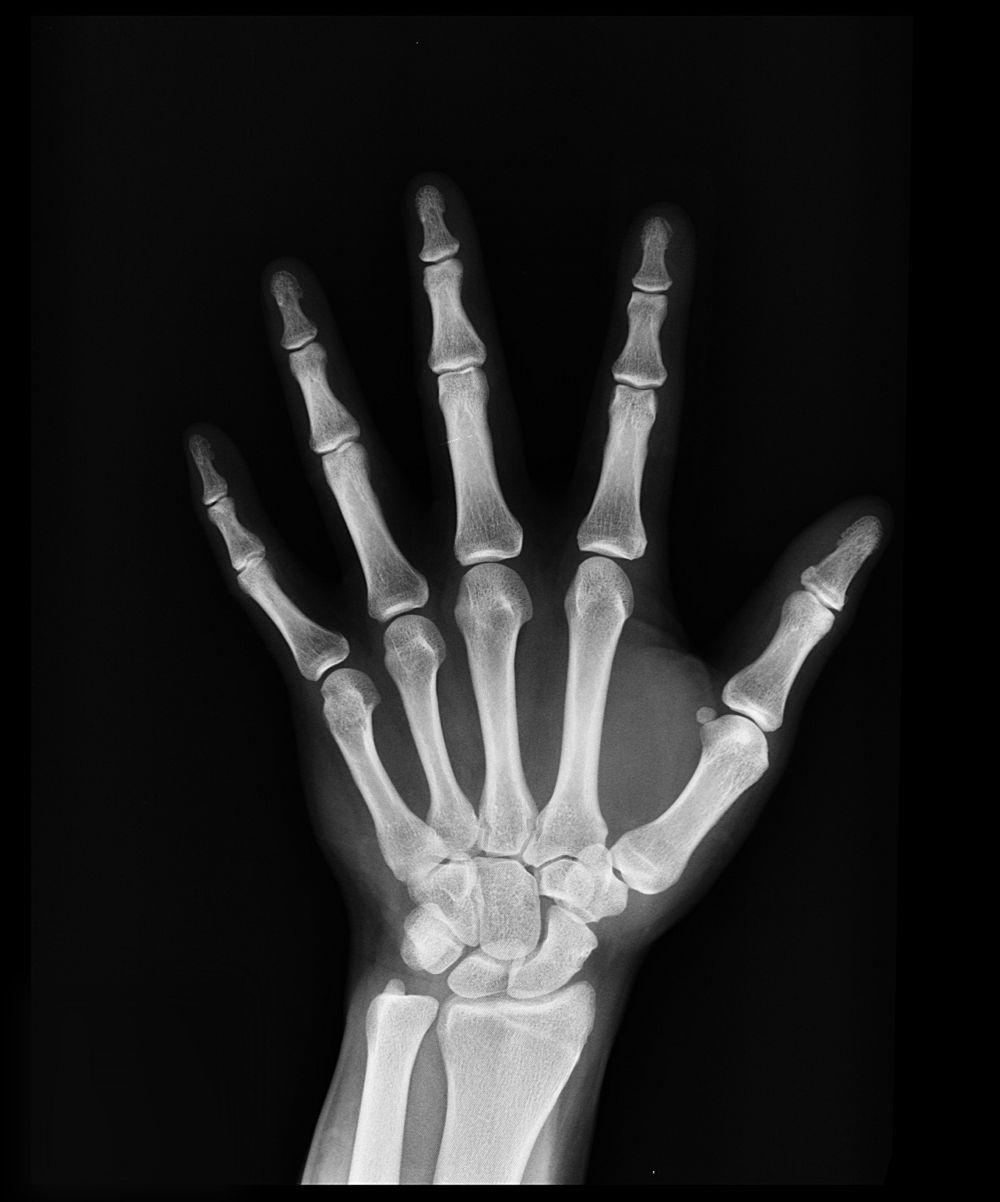

Røntgenundersøgelse